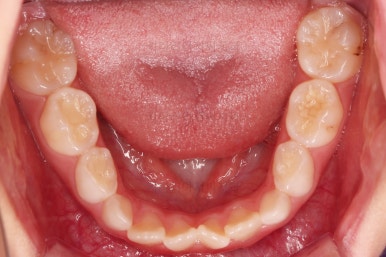

총 13개월 걸려서 부산초등학생교정 위턱의 3차원적 성장과 앞니 가지런함을 다 이뤘어요.

앞니의 반대교합 뿐만 아니라 어금니 반대교합도 개선되었네요.